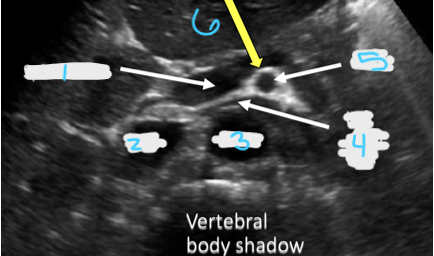

<p>In this transverse view, what is #1?</p>

In this transverse view, what is #1?

Aorta

<p>In this transverse view, what is #2?</p>

In this transverse view, what is #2?

Common Hepatic Artery

<p>In this transverse view, what is #3?</p>

In this transverse view, what is #3?

Left Splenic Artery

<p>In this transverse view, what is #5?</p>

In this transverse view, what is #5?

SMA

<p>In this transverse view, what is #6?</p>

In this transverse view, what is #6?

Splenic vein